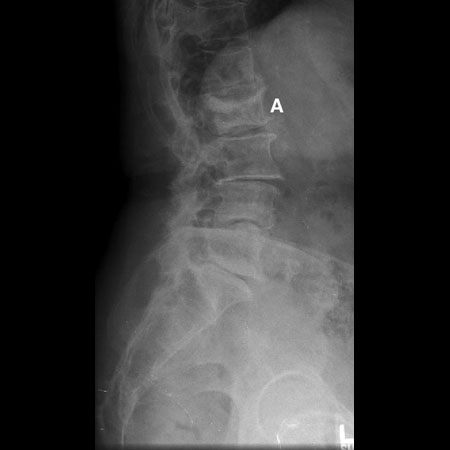

Radiografia do tumor: linfoma (A) destruindo a vértebra L5

Cortesia do Dr K. Singh; usado com permissão